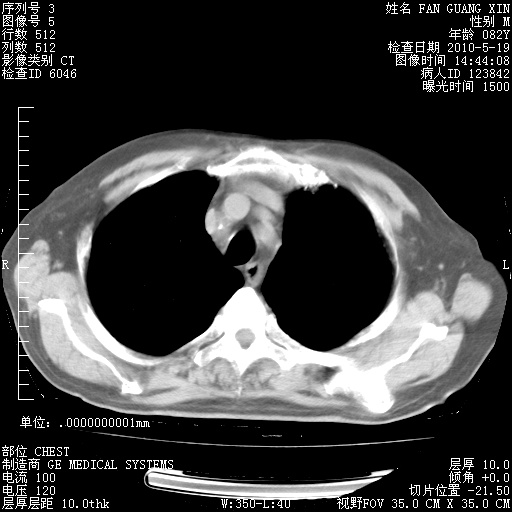

可改为口服强的松40-50mg/d治疗,若病情仍稳定,胸部阴影不再吸收可逐渐减量